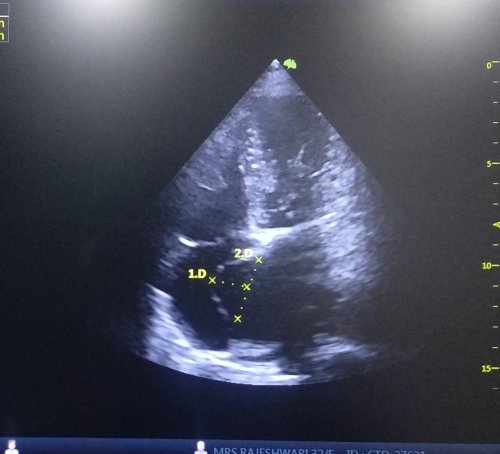

The most common mechanism proposed for palpitation is hyperactive anterior mitral leaflet

Mitral stenosis patients can feel their loud first heat sound (S 1) or varying S1 during atrial fibrillation as palpitation; Mitral valve prolapse with redundant , hyper kinetic motion is probably most common cause of benign palpitation.

Sclerosed and calcific valves attenuates palpitation. Calcific mitral valve in mitral stenosis make both S 1 intensity and opening snap feeble .These patients are less likely to feel palpitation .